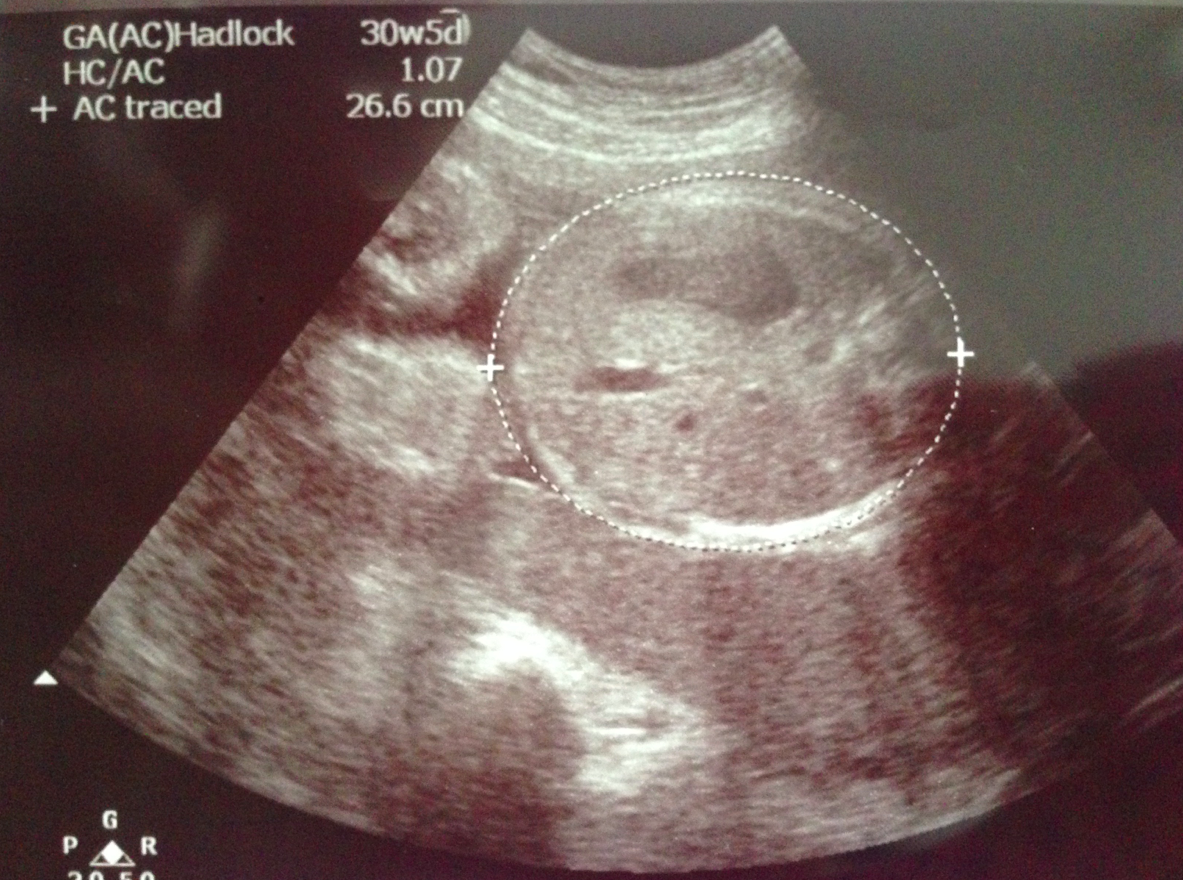

指定動作﹗頭仔先~而家頭仔直徑有7.71cm,超聲波機計算嘅週數係31w3d,S醫生話而家嘅週數嚟講正負兩星期都屬於正常~

脾長就30w1d~

睇落好似大脾相對頭仔同肚仔細啲size,除咗measurement肯定會有嘅少少誤差之外,其實我哋都要考慮到超聲波機係西方國家出品,所以佢哋內部既定嘅週數都係用番西方BB嘅標準,我哋plot番落graph就可以睇到BB呱嘅生長啦~

頭仔同肚仔繼續along 50 percentile,但脾長好似飄咗上去長腿嗰邊?﹗我哋兩個都一致認為即使BB呱長腿都肯定係「暫時性」,佢都冇長腿基因,將來應該都係短腳㗎啦~anyway,BB呱整體都長得好好﹗感恩~